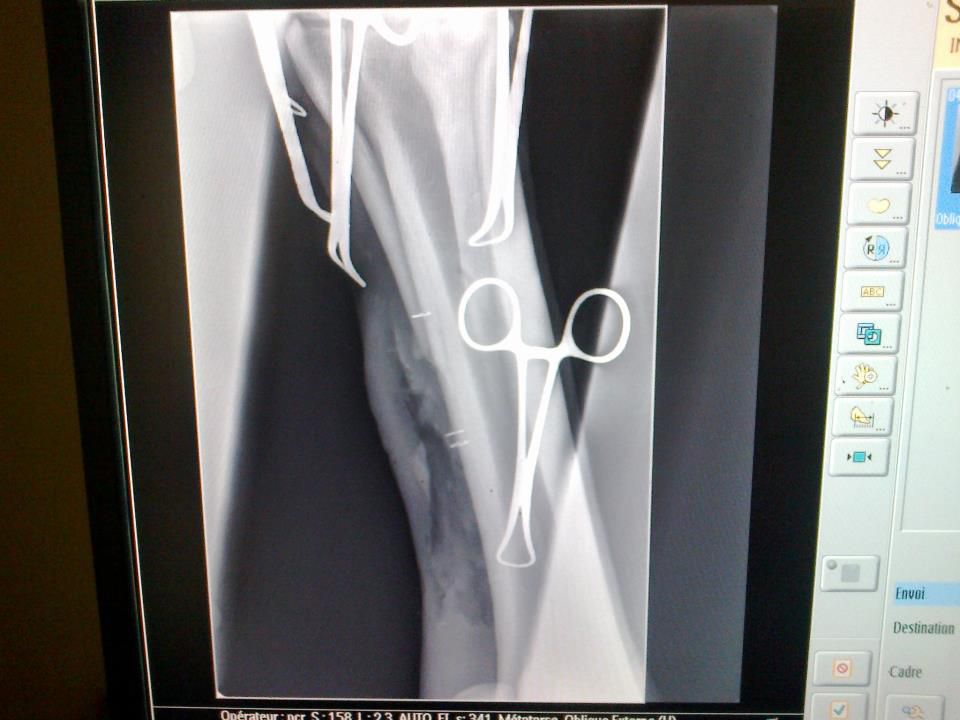

| Dire merci | hihi je passais pour vous montrer les vidéos que j'ai faite pdt l'opération, mais je vois que vous êtes déjà au courant! heureusement ya tata Nesta qui fait les potins! Donc oui fracture du rudimentaire, un coup de cul, il a envoyé le postérieur dans la barrière de la carrière, c'est ça quand on est un petit (grand?) couillon qui veut pas travailler..... avant l'opération : on voit bien entre les agraphes l'os bien broyé ![]() après : ![]() et les vidéos : âmes sensibles s'abstenir... Lien Lien Lien Lien Lien |